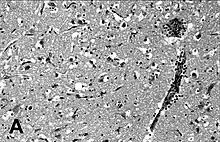

![]() | |

Immunohistochemical staining of the lung of a seal with PDV infection | |